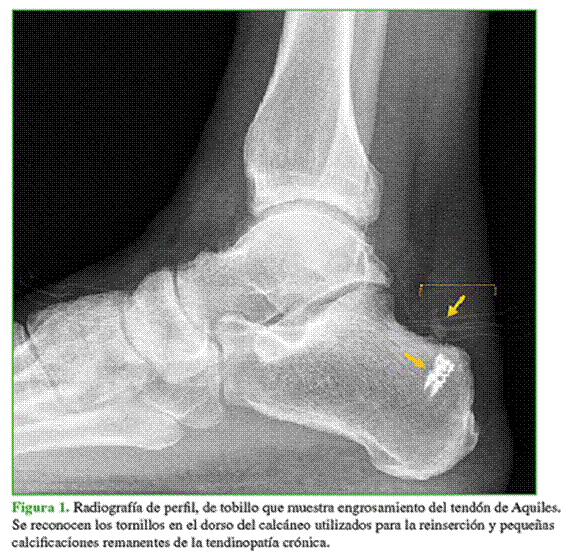

La RM confirma los hallazgos de tendinopatía crónica sin cambios de señal significativos en la inserción distal (Figuras 2 y 3).